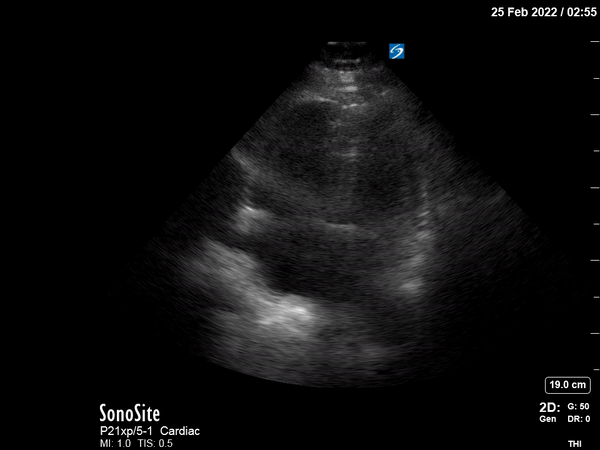

POCUS shows multiple findings consistent with acute right ventricular

(RV) systolic failure in the setting of increased RV afterload.

Parasternal long and short axis views show severe RV dilation,

flattening of the interventricular septum during systole and diastole,

and compromised LV filling. The parasternal long axis also demonstrates

dynamic obstruction of the LV outflow tract caused by systolic anterior

motion of the mitral valve (SAM), inadequate LV preload, displacement of

the interventricular septum, and tachycardia. The apical four-chamber

view shows a dilated RV with a McConnell sign (paradoxical RV apical

“hyperkinesis” in the setting of RV global hypokinesis).2